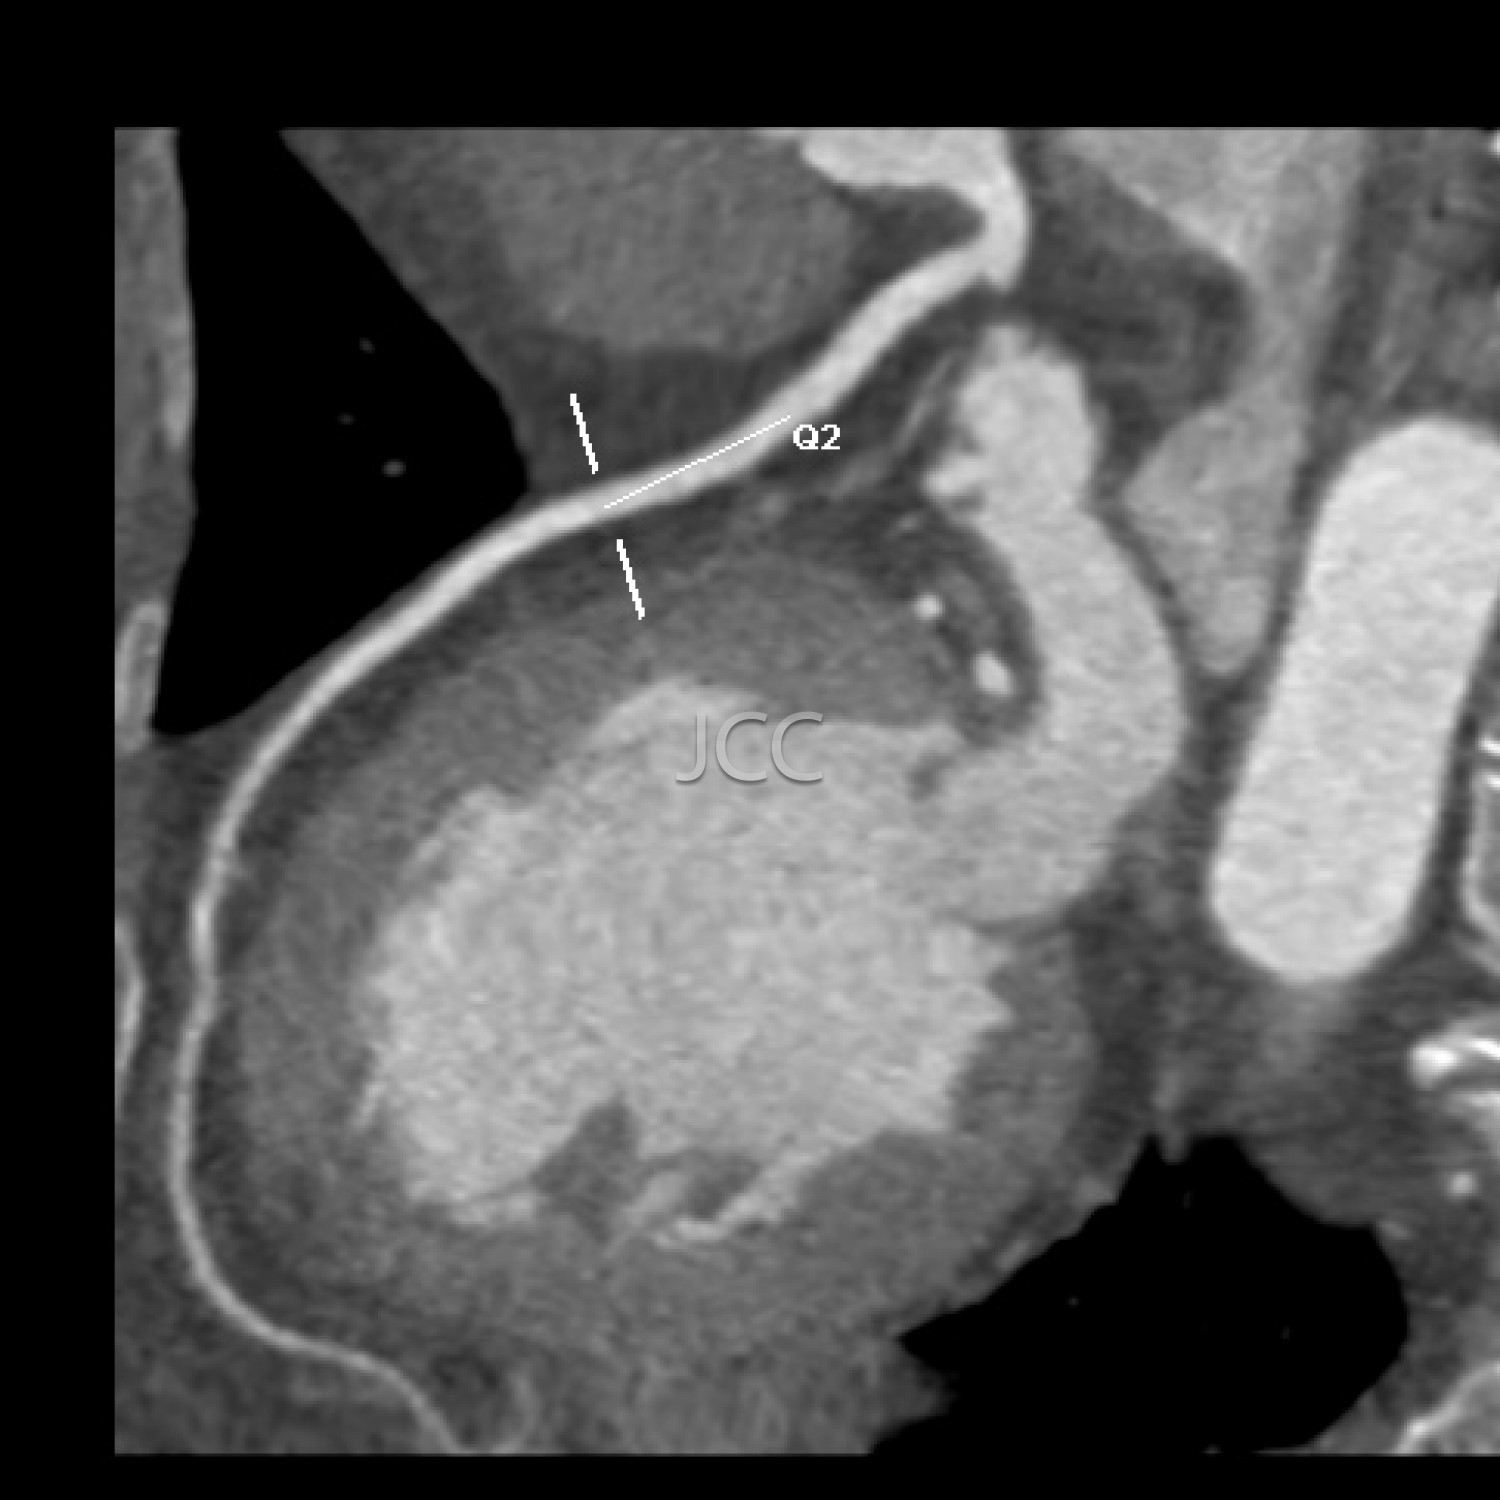

Tomografia Axial Computorizada - ANGIO TAC CORONÁRIAS

A Tomografia Axial Computorizada (TAC) - Dupla Energia - 256 cortes é uma técnica de diagnóstico que permite a avaliação de várias partes do corpo humano, incluindo pulmões, fígado, pâncreas, rins, coração, estruturas vasculares e estruturas ósseas.

Os nossos equipamentos são todos de multicorte permitindo avaliação em alta definição e baixa dose de radiação incluindo o estudo das coronárias.